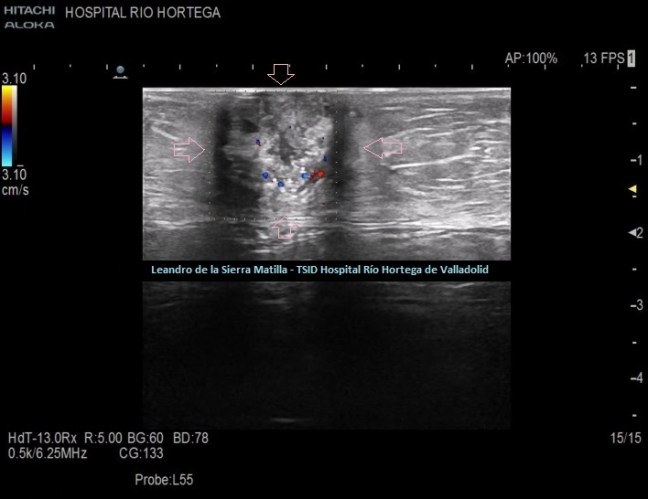

Durante el estudio del peritoneo, retroperitoneo y cadenas linfáticas abdominales, observamos una lesión superficial, redondeada, heterogénea, hipo-Isoecogénica con zonas hiperecogenicas, de aspecto sólido.(FIGURA 4)

4

Cambiamos a una sonda lineal para un estudio más detallado, observando una LOE hipoecogénica con zonas híper-isoecogénicas, heterogénea, sólida, sin contenido de asas intestinales ni de grasa, con bordes mal definidos y con flujo doppler en su interior, ubicada dentro de la cavidad umbilical (FIGURAS 5, 6 Y 7)

5

6

7